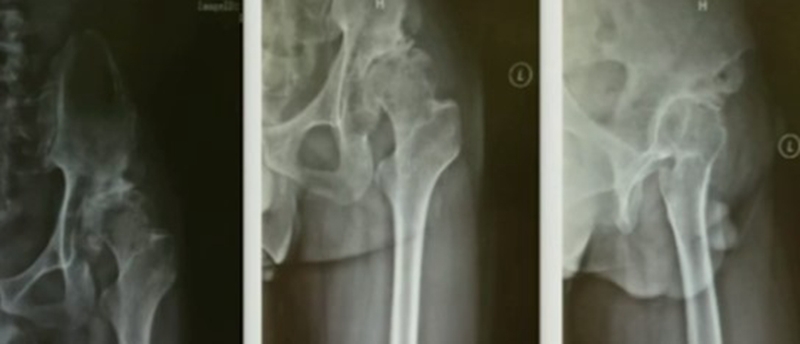

导致股骨近端畸形的原因主要有原发型和继发型两大类。原发型多为发育异常所致(DDH)、代谢性骨病、强直性脊柱炎引起;继发型主要为手术所致,包括股骨近端截骨术、股骨近端骨折内固定术、全髋或半髋置换,其他因素如感染、创伤畸形愈合等。

二、股骨近端畸形的分型---Berry分型

继发畸形多种多样,很少有病例与分型完全一致,但其核心要素是畸形位置和畸形类型。

畸形位置:大粗隆、股骨颈、干骺端、股骨干

畸形类型:成角畸形、旋转畸形、横行畸形、髓腔异常

Ⅰ、大粗隆畸形

(1)悬突型:大粗隆过度增生或移位,偏向内侧或前后方。

阻挡髓腔开口,内外旋时,大粗隆边缘与髋臼发生撞击;根据髓腔延长线开口,去除大粗隆多余骨质,去除大粗隆前后方骨赘,避免骨性撞击。

(2)高骑跨型:大粗隆位置高耸

大粗隆尖与髋臼边缘撞击,如果在肢体等长情况下,撞击仍无法避免,需要考虑大粗隆滑移截骨。

Ⅱ、股骨颈畸形---髋内外翻,offset异常

(1)颈干角偏小(<120°)——髋内翻

髋内翻,颈干角小,偏心距较大,选择high-Offset假体,以维持外展肌张力。

(2)颈干角过大(>140°) ——髋外翻

髋外翻多见于DDH,难度在于股骨距内侧皮质阻挡假体完全坐入髓腔,强行打击造成股骨距骨折。

Ⅲ、干骺端畸形

硬化骨、骨赘、骨质疏松、髓腔宽大

转子间骨折畸形愈合后常导致干骺端畸形,干骺端遗留大量硬化骨或髓腔成角,术中需在确认髓腔开口位置后,首选用小骨刀或高速磨钻去除硬化骨,打通髓腔。